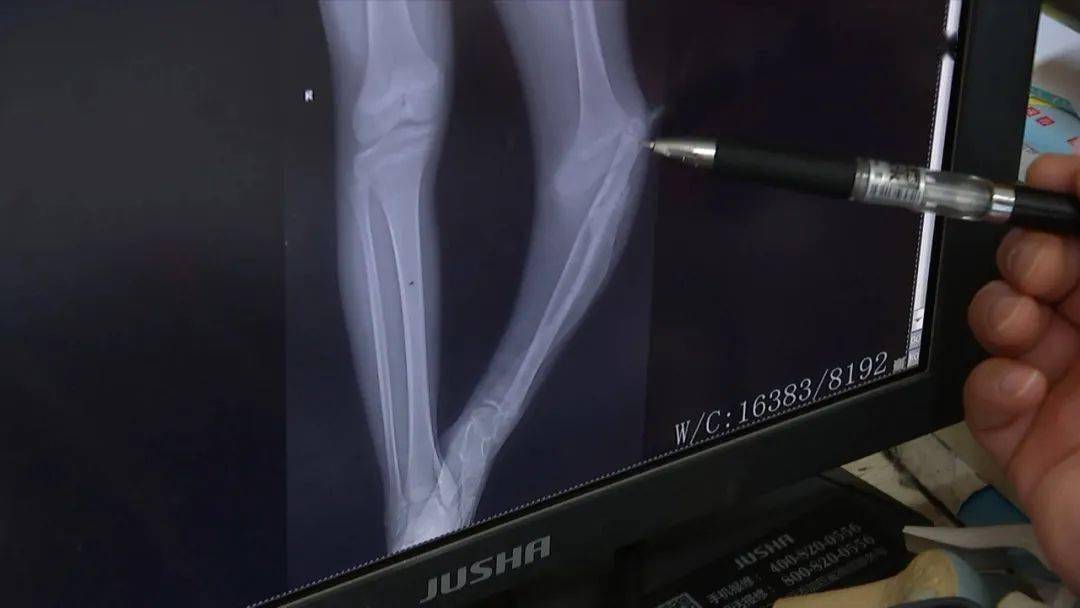

片:当时病人外踝部轻度肿胀,无明显压痛,相当于腓骨弯曲部位压痛明显

浙江省荣军医院(嘉兴三院)手足外科主任 黄显军:你这个腓骨,现在跑到